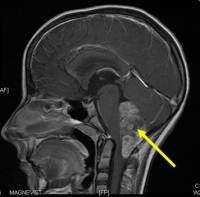

Ведущая частная Израильская клиника «Ассута» предоставляет своим пациентам возможность пройти все применяемые на сегодняшний день в Израиле виды медицинских обследований, в том числе компьютерную томографию (КТ), позитронно-эмиссионную томографию с КТ (ПЭТ-КТ), магнитно-резонансную томографию МРТ, а также рентгенографию, ультразвук, маммографию и другие способы визуализационной диагностики.Если вам была выполнена биопсия, мы готовы пересмотреть ее результаты - привезите с собой блоки/стека для пересмотра нашим патологом. Экспресс-анализ занимает порядка 3 суток, в большинстве случаев выполняется повторное окрашивание препарата. "Ассуту" отличает высочайшее техническое качество обследований, которое достигается скрупулезным соблюдением протокола выполнения процедур, и максимальное качество расшифровки данных, что обеспечивается работой радиологов исключительно в рамках их специализации.

Известно, что высокоактивные раковые клетки более интенсивно поглощают молекулы контрастного вещества, и излучение, которое в результате исходит от этих клеток, проявляется на экране ПЭТ-установки в виде светящихся точек, что позволяет выявить даже миллиметровые опухолевые структуры. Последующее применение КТ позволяет выяснить точное расположение опухоли. Оба этих метода медицинской визуализации прекрасно дополняют друг друга. Установка ПЭТ - единственный в мире аппарат, позволяющий диагностировать опухоль на так называемой нулевой стадии. Кроме того, благодаря процедуре ПЭТ-КТ у пациента можно обнаружить и иные отклонения от нормы, в частности, эндокринологические и неврологические, а уровень получаемого при этом облучения минимален. Результат сканирования проходит двойную расшифровку - врачом-радиологом и специалистом по ядерной медицине.Мы – единственная клиника в Израиле, где качество работы контролируется избирательными двойными проверками качества медицинских услуг и безопасности пациента.